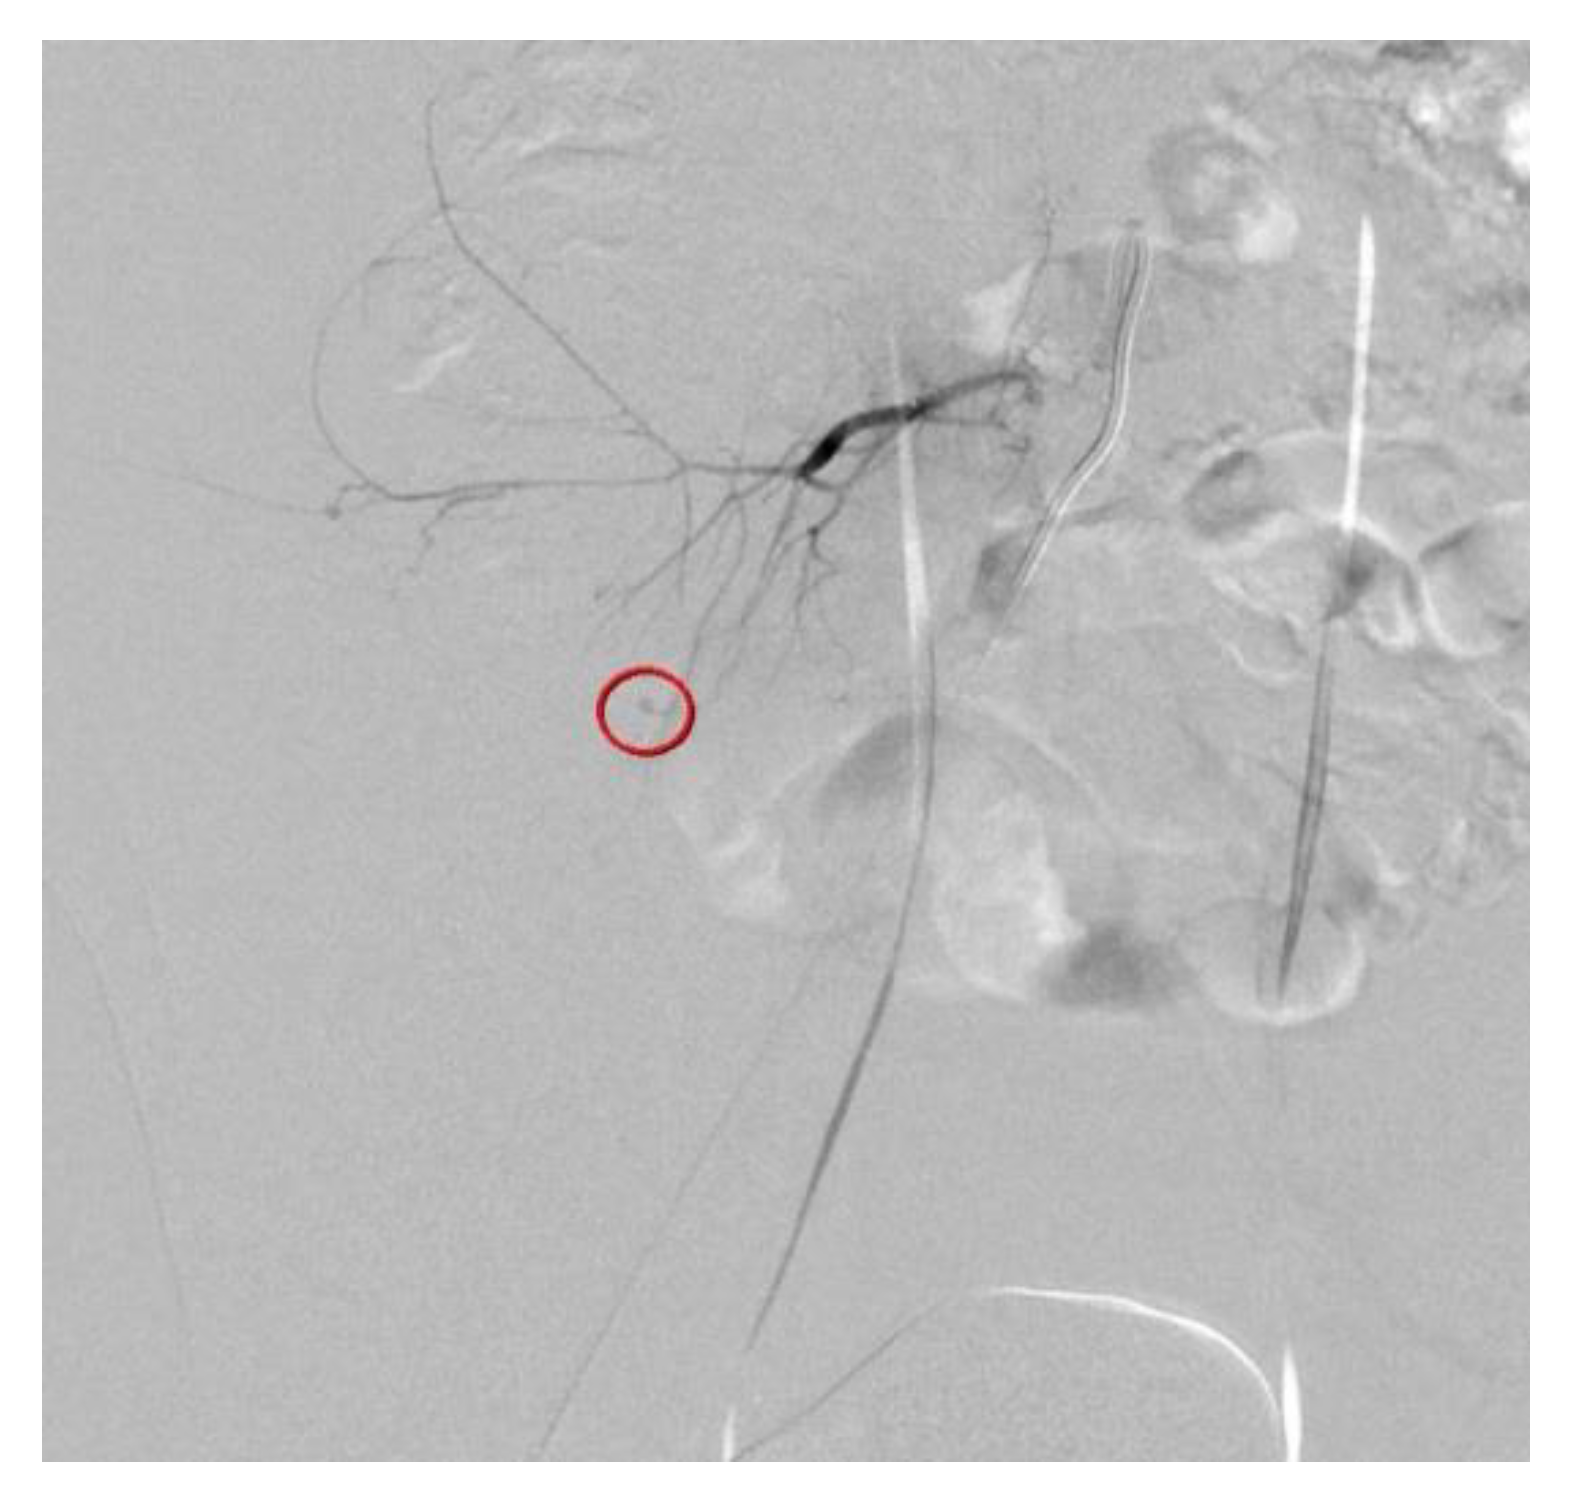

Figure 3. Transcatheter arterial embolization (TAE) of the ruptured fifth lumbar artery was successfully performed using Gelfoam particles (Figure 3). The patient recovered uneventfully and was discharged 4 days after TAE, without any complications or blood transfusion. After 1 month of follow-up, the patient recovered uneventfully, and no hemorrhage-related complications were observed. Iatrogenic lumbar artery injury during PDN is rare, but may be a serious condition that requires early detection and urgent treatment. Great care should be taken to avoid hemorrhagic complications, and adequate an technique and anatomical considerations are important to avoid these complications. Transarterial embolization, rather than open hematoma evacuation or laparotomy, can be a safe and effective treatment to stop active bleeding. Successful embolization of the bleeding vessel is performed using Gelfoam particles (circle).